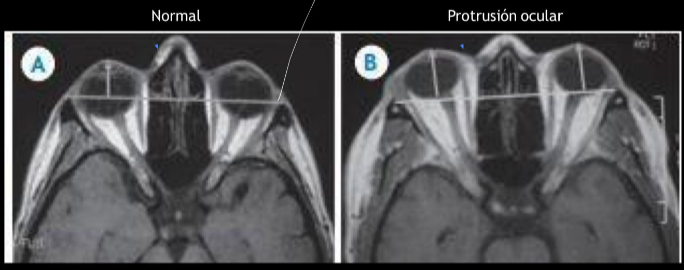

RM exoftalmos

RM

- protusion ocular anormal

- disociacion indice globo ocular - linea intercantal

- masa ocupativas retroculares